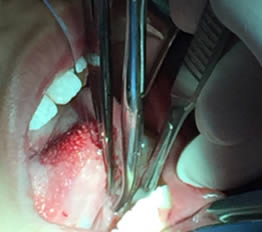

• Se eliminó el frenillo en su totalidad  con la ayuda de tijeras iris recta y hoja de bisturí del No. 15 así como todo el tejido residual fibroso correspondiente al frenillo. Se realizó genioplastia con pinza de mosco y disección roma para liberar adecuadamente la inserción frénica hasta la cara lingual de los incisivos inferiores. (Figuras  7, 8 y 9)

Figuras 7 y 8. Eliminación total del frenillo y genioplastia